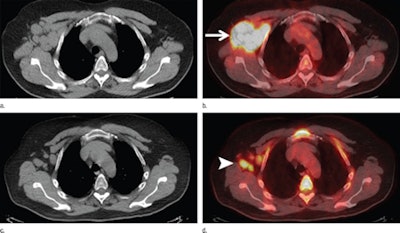

PET/CT scans were performed from midskull to upper thigh approximately 60 minutes after intravenous administration of 12 mCi to 15 mCi of FDG. All imaging exams occurred within the three months before stem cell transplantation at Memorial Sloan Kettering, between January 2005 and December 2010.

Ulaner, who was blinded to the results, analyzed the original FDG-PET/CT images, taking note of suspicious FDG-avid lesions and the maximum standardized uptake value (SUVmax) of the most avid lesion.

The researchers considered patients with suspicious FDG-avid lesions to be PET-positive and have an active malignancy, while non-FDG-avid lesions were considered a PET-negative result.

Among the 73 subjects in the allogeneic group, 23 had FDG-avid lesions and 50 had PET-negative results. Of the 102 autologous stem cell transplant patients, 11 had FDG-avid lesions and 91 had PET-negative results.